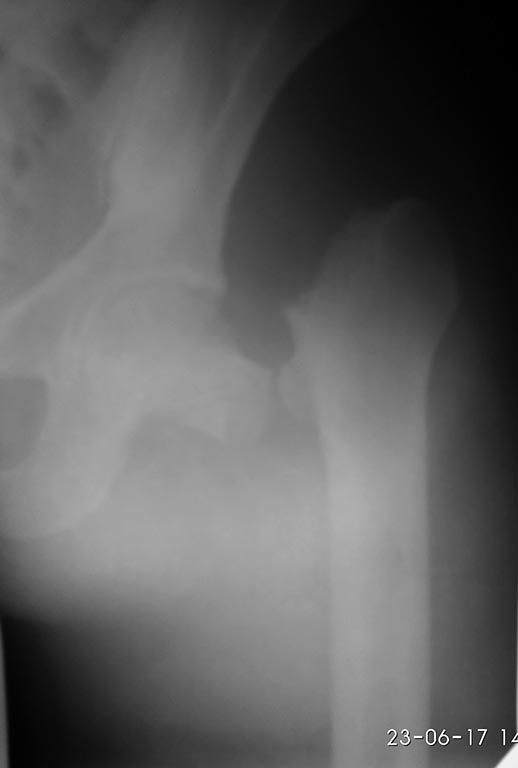

Коллеги, подскажите оптимальную тактику. Мотоциклист, 30 лет,

политравма, ЧМТ, перелом лицевого скелета, открытая проксимальная голень

и ипсилатеральная шейка бедра. Более недели в РАО. На данный момент

стабилен,переведен в отделение. Вопрос по шейке, срок упущен, да и

повреждение с максимальным нарушением кровоснабжения,что оптимальный -

синтез или первичное эндопротезирование? Мнения разделились.